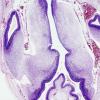

DEVELOPMENTAL MALFORMATIONS

Brain, normal, developmental

Fetus - 7-8 weeks